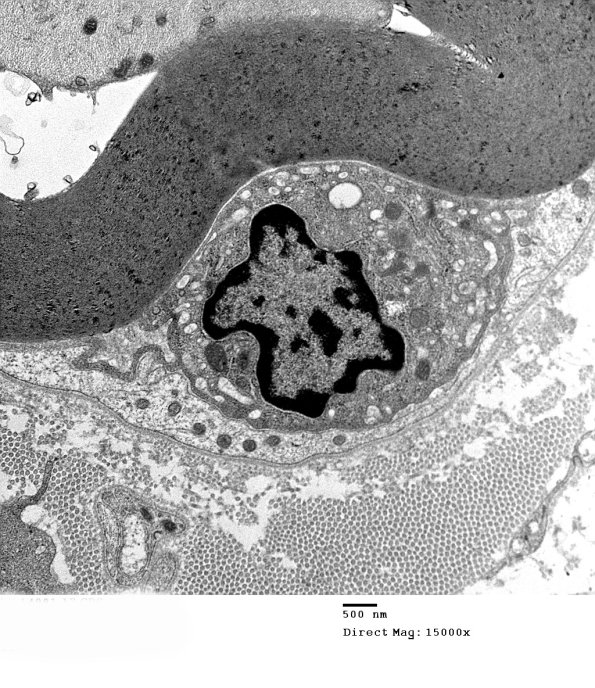

Early macrophage invasion. (electron micrograph)